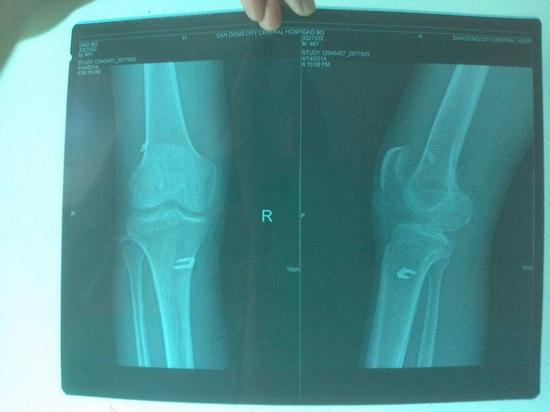

比如X光照射可以了解车祸病人的骨折情况,加快确诊与治疗的速度,有效的挽救患者性命,又比如同是医疗检查项目的CT检查,也存在轻微辐射量,但是危害性较小,并有效的解决了脑部疾病难以诊断的问题。